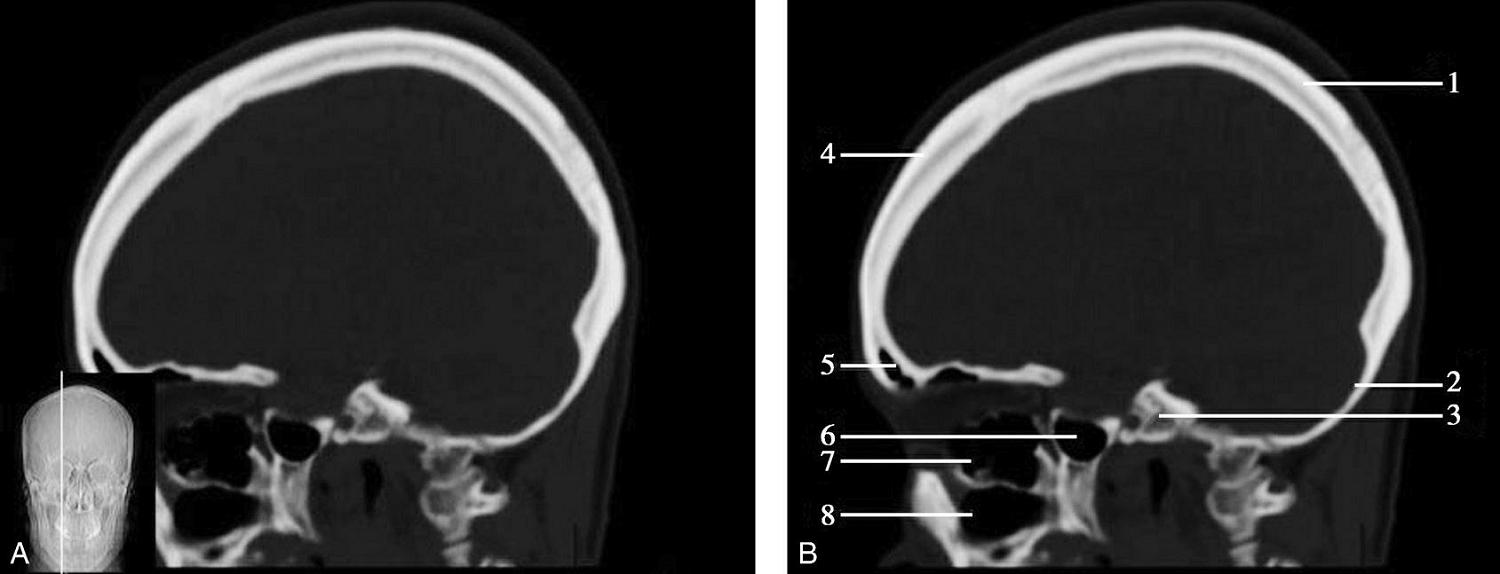

图1-2-60 正中矢状面骨窗CT

A.矢状面;B.矢状面标注

1.顶骨;2.枕骨;3.斜坡;4.额骨;5.蝶鞍